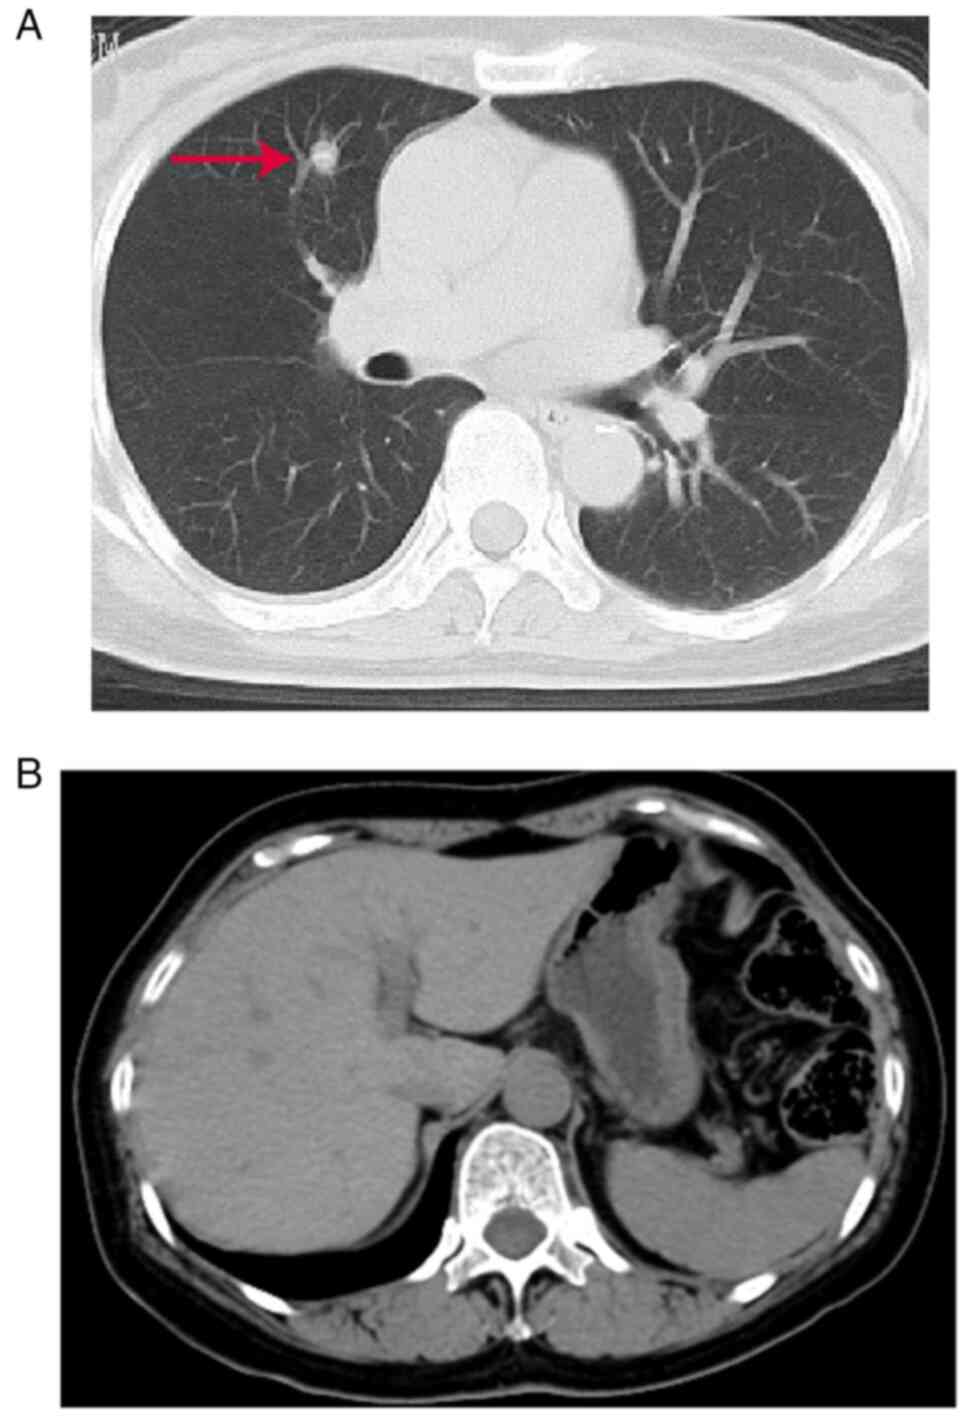

Metastatic thyroid cancer is rare. Here, the case of a patient with colon cancer that metastasized to the thyroid is described. The patient underwent radical rectal cancer surgery in August 2017 and received six cycles of chemotherapy with oxaliplatin and capecitabine postoperatively. On August 4, 2018, the patient was admitted to the hospital due to the discovery of thyroid nodules on ultrasound and carcinoembryonic antigen levels within the normal range. The biopsy from the fine needle aspiration suggested a malignant tumor. The patient underwent radical thyroid cancer surgery. Using intraoperative rapid frozen pathology, medullary carcinoma was diagnosed. Using postoperative routine pathology combined with immunohistochemistry results, thyroid metastasis from colorectal adenocarcinoma was diagnosed. After surgery, the patient regularly visited the outpatient clinic for chemotherapy with capecitabine. As of May 2023, the patient is still alive with no recurrence.

Figure 1

Figure 2